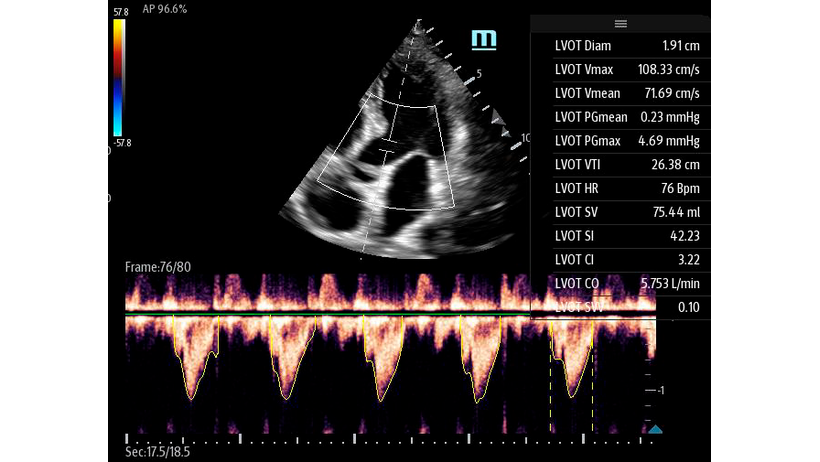

Чтобы использовать уравнение, нужно получить поток выносящего тракта левого желудочка в PW допплере — это достаточно кропотливая работа. В ультразвуковых системах Mindray Resona i9 эта задача решается автоматической оценкой потока выносящего тракта – Smart VTI.

Доктору остается получить 5-ти камерное сечение сердца и нажать одну кнопку на сенсорном экране. Прибор сам выберет расположение контрольного объема, получит спектрограмму и обведет спектр с расчётом всех показателей. Быстро и эффективно.